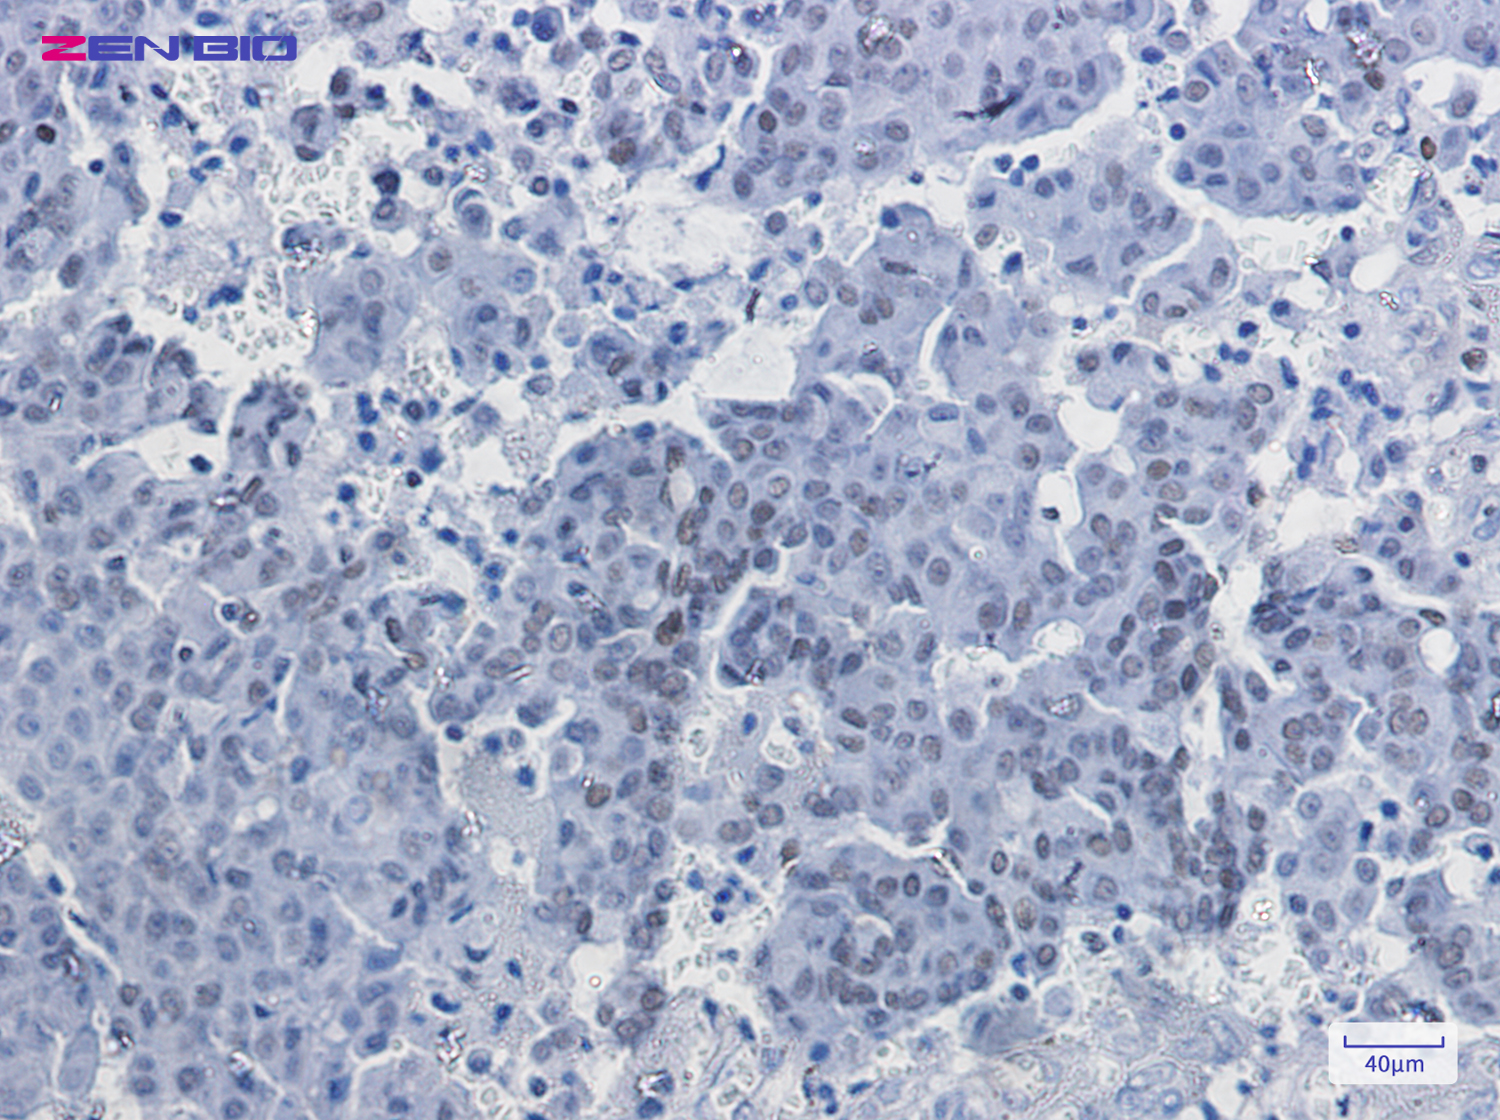

Immunohistochemistry of RUNX1/2/3 in paraffin-embedded Human breast cancer tissue using RUNX1/2/3 Rabbit pAb at dilution 1/50